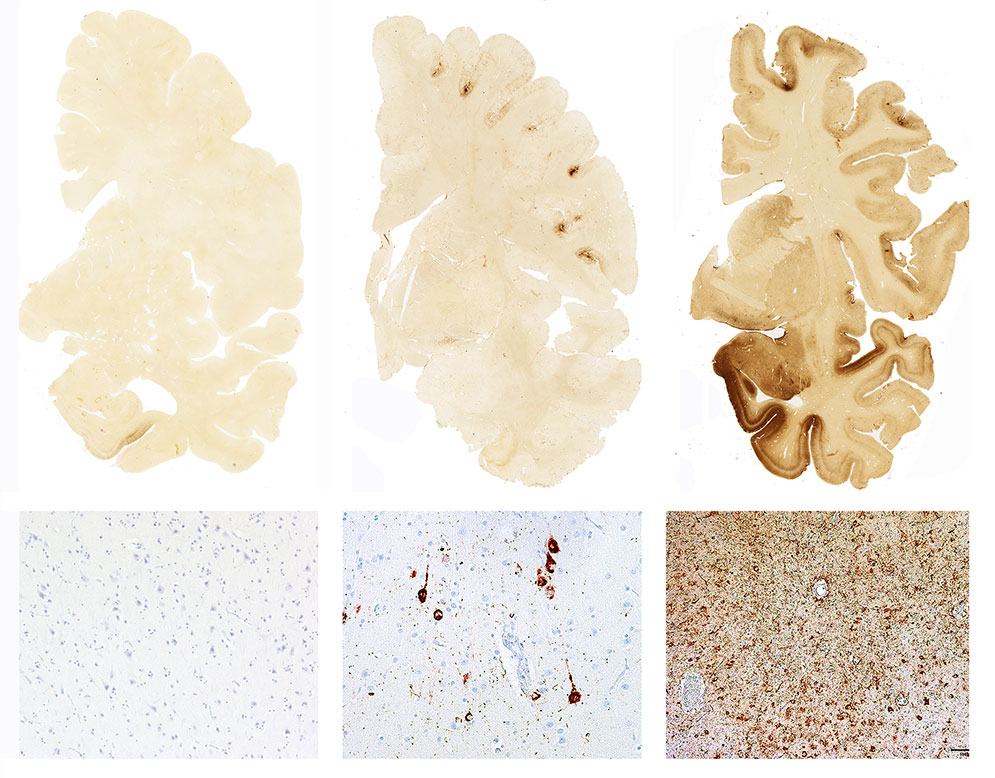

CTE develops in brains that sustain repeated trauma, as the soft tissues of the brain hit the hard bone of the skull repeatedly. Football players, boxers, and other contact athletes suffer these kinds of hits, as do people subjected to violence under other circumstances. The damage to the brain is caused by clumps defective tau proteins, which kill neurons; it’s a similar process to the progression of Alzheimer’s disease. However, in the case of CTE, the damage itself may be done early in life, while symptoms might not be noticeable for years, or even decades.

There is no way to know exactly how prevalent CTE is among the general population, or even among those populations most likely to have it, given the difficulty in diagnosing it. However, we are currently learning more about the problem. Earlier this year, a study from BU Medical School’s Chronic Traumatic Encephalopathy Center revealed that all but one of 111 brains of NFL players donated for analysis had some form of CTE. Research has also found connections between combat service, traumatic brain injury, CTE, and post traumatic stress disorder among veterans.